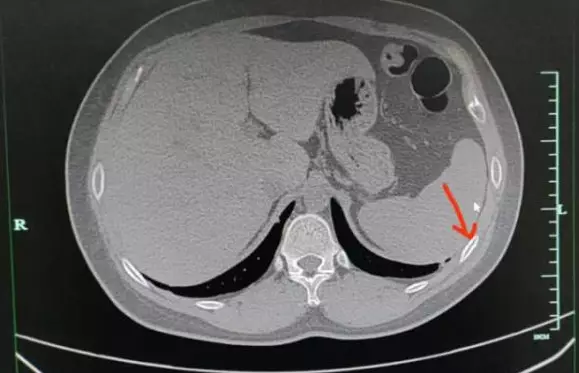

聶先生透露,「一開始只是咳嗽,本以為過陣子就會自然康復,沒想到後來越來越嚴重,後來甚至咳到胸部陣陣疼痛,每次一咳胸就好像被錘子敲打一樣疼痛」,十分難受。後來他實在忍不住去醫院治療,醫生經CT掃描發現聶先生胸右側的第五、六根肋骨骨折了,詢問又得知聶先生平時的作息和飲食都不規律,工作壓力很大。

醫生解釋道,「肋骨骨折並不承受重量,所以在靜止狀態下通常不會覺得痛。但當肋骨受到外力壓迫或胸廓活動較大,如咳嗽或深呼吸時就會引起劇痛」。醫生又指出,因咳嗽造成肋骨斷裂的情況在骨質疏鬆的老年人患者中較常見,因此推斷由於聶先生的不良生活習慣導致疲勞,「令肋骨反復受到拉扯導致疲勞性骨折」。